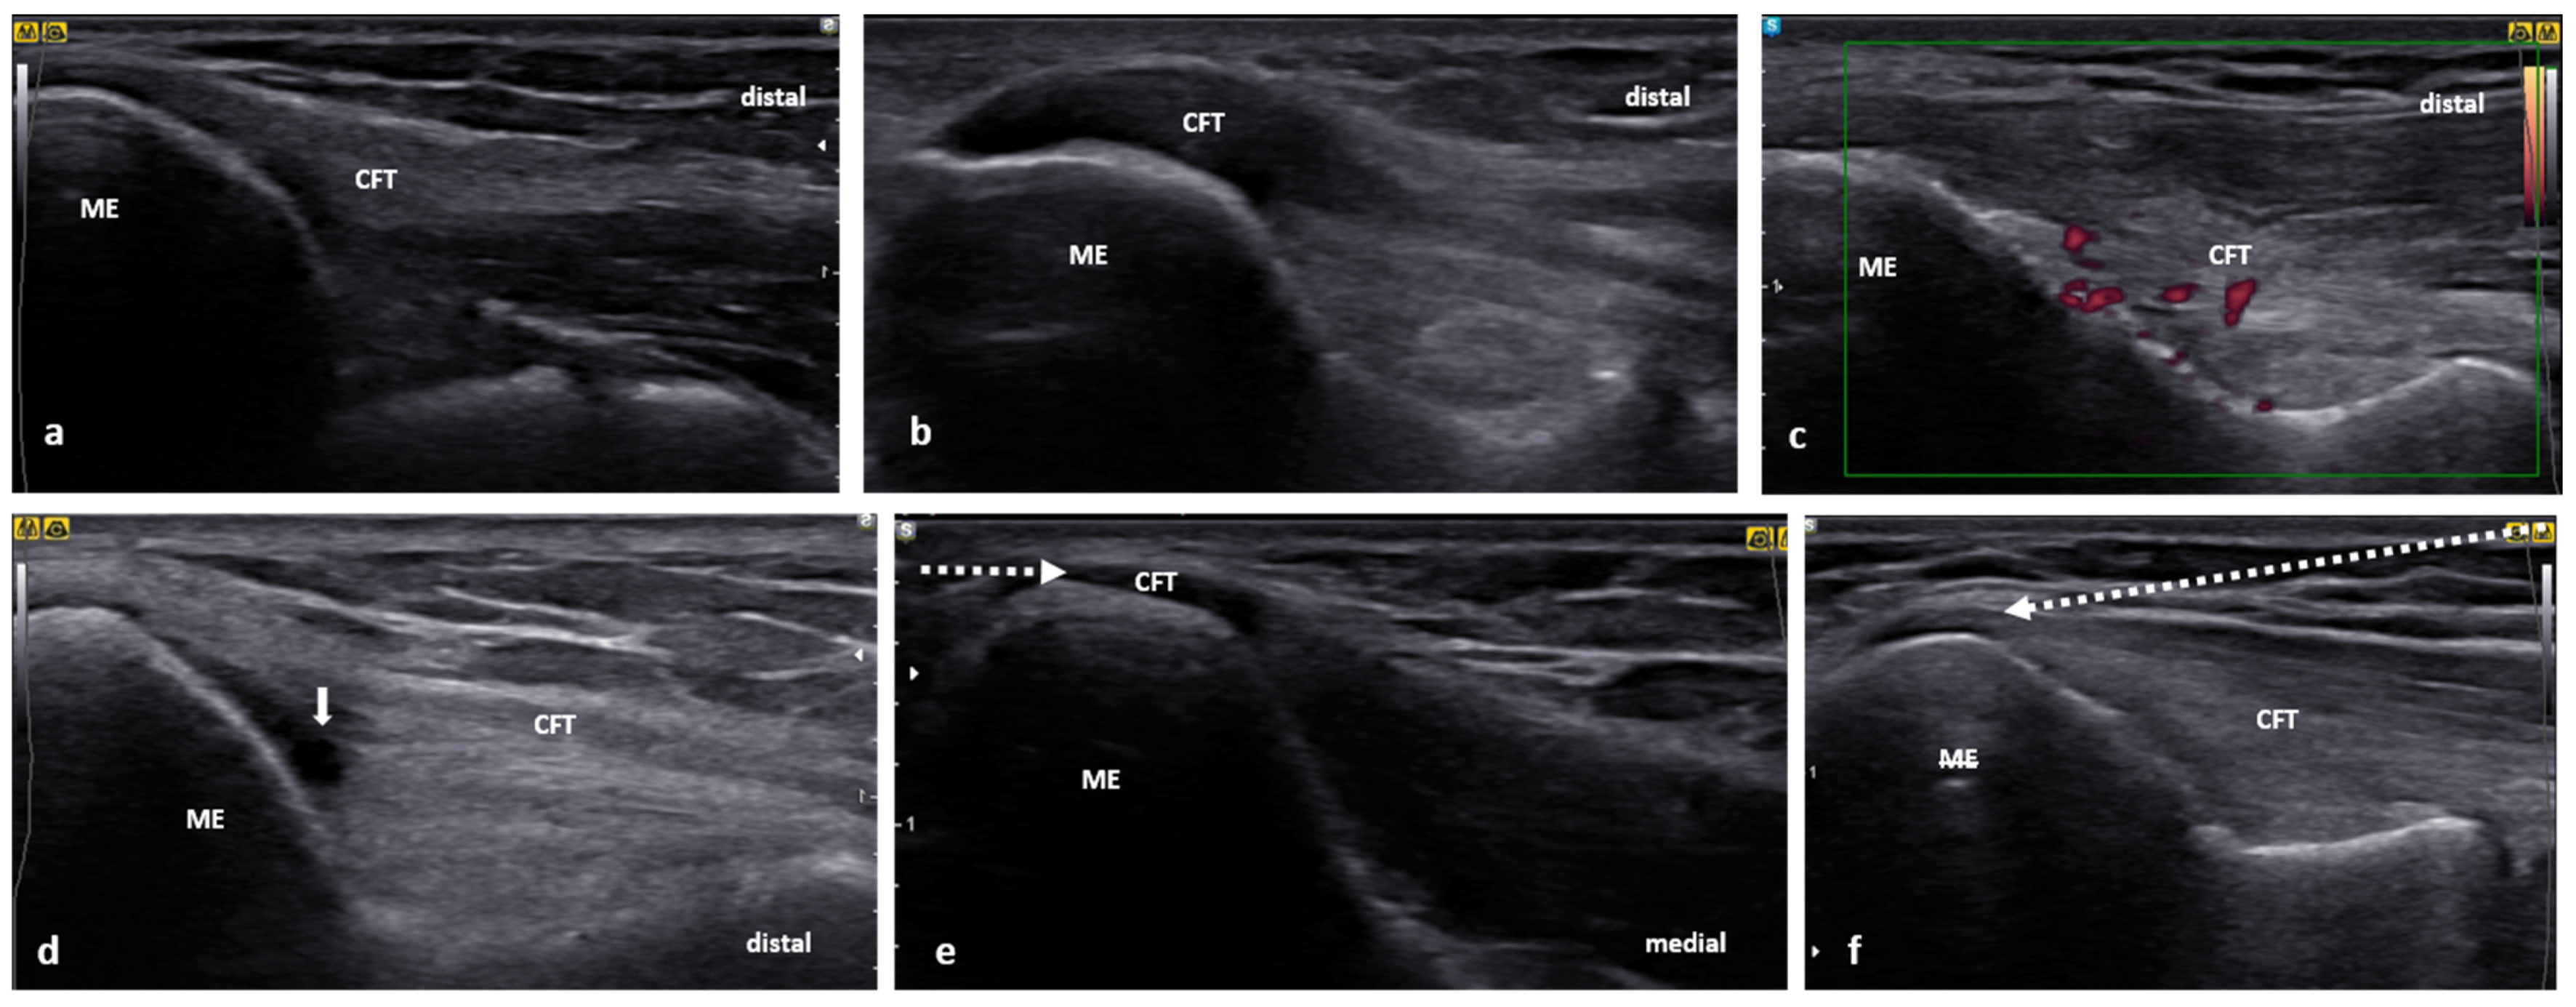

For US scanning of the CFT, the patient may be positioned semi-supine on the examination bed while the patient’s arm is resting on the bed with the forearm hanging over the bed’s edge. As an alternative, the patient may sit facing the examiner, leaning to the ipsilateral side with the supinated forearm resting on an examination bed. To obtain the longitudinal view of the CFT, the transducer is placed at the medial humeral epicondyle (ME) along the forearm’s long axis. The important bony landmarks would be the ME and coronoid process of the ulna. Superficial to these bony structures, the anterior bundle of the MCL and CFT can be identified (Figure 6a). Compared to CET, the CFT is broader and shorter. Normally, the CFT is proximally noncompressible and compressible distally while the softer muscle tissue prevails the stiffer tendon. A sensitivity and specificity of 95% and 92%, respectively, have been reported for the detection of clinical golfer’s elbow. Characteristic US images of medial epicondylitis show focal areas of hypoechogenicity [59]. Typically, the swelling in a golfer’s elbow is located very proximally (Figure 6b) [15]. Further signs, such as tendon thickening, cortical irregularities, intratendinous calcifications, and hypervascularity, are also common (Figure 6c,d). Notably, lesions of the anterior bundle of MCL can mimic or be concurrent with medial epicondylitis. In such a scenario, US imaging would reveal MCL structural abnormalities, e.g., thickening and discontinuity. Notably, the dynamic US valgus stress test might be beneficial to demask MCL rupture, coupled with elbow instability [19].

Figure 6.

Ultrasound images of the CFT: (a) normal image of the CFT, (b) a severe thickening and hypoechogenicity of the CFT, (c) US image demonstrating degenerative changes and hypervascularity in the CFT, (d) small ganglion (white arrow) in the CFT, (e) US-guided peritendinous CET injection showing the needle (white, dotted arrow) being inserted from medial to lateral in a short axis of the CFT, (f) the needle (white, dotted arrow) can also be inserted from distal to proximal along the long axis of the CFT.

For the golfer’s elbow injection, the patient may be positioned in the prone while his or her forearm also rests pronated on the examination bed (Figure 7). The probe is positioned on the medial epicondyle perpendicular to the long axis of the forearm. The needle is inserted from lateral to medial. Again, depending on the particular procedure plan, the injection can be performed peri- or intratendinous. The parallel course of the needle to the probe provides excellent needle visibility along its whole path (Figure 6e). Alternatively, the needle can be inserted from distal to proximal (Figure 6f). When injecting a golfer’s elbow, one should take caution not to pierce the ulnar nerve, particularly in cases of ulnar nerve anterior dislocation [67] or in patients who underwent ulnar nerve anterior transposition surgery. Using US imaging, the safe needle route can be determined proceeding with the intervention.